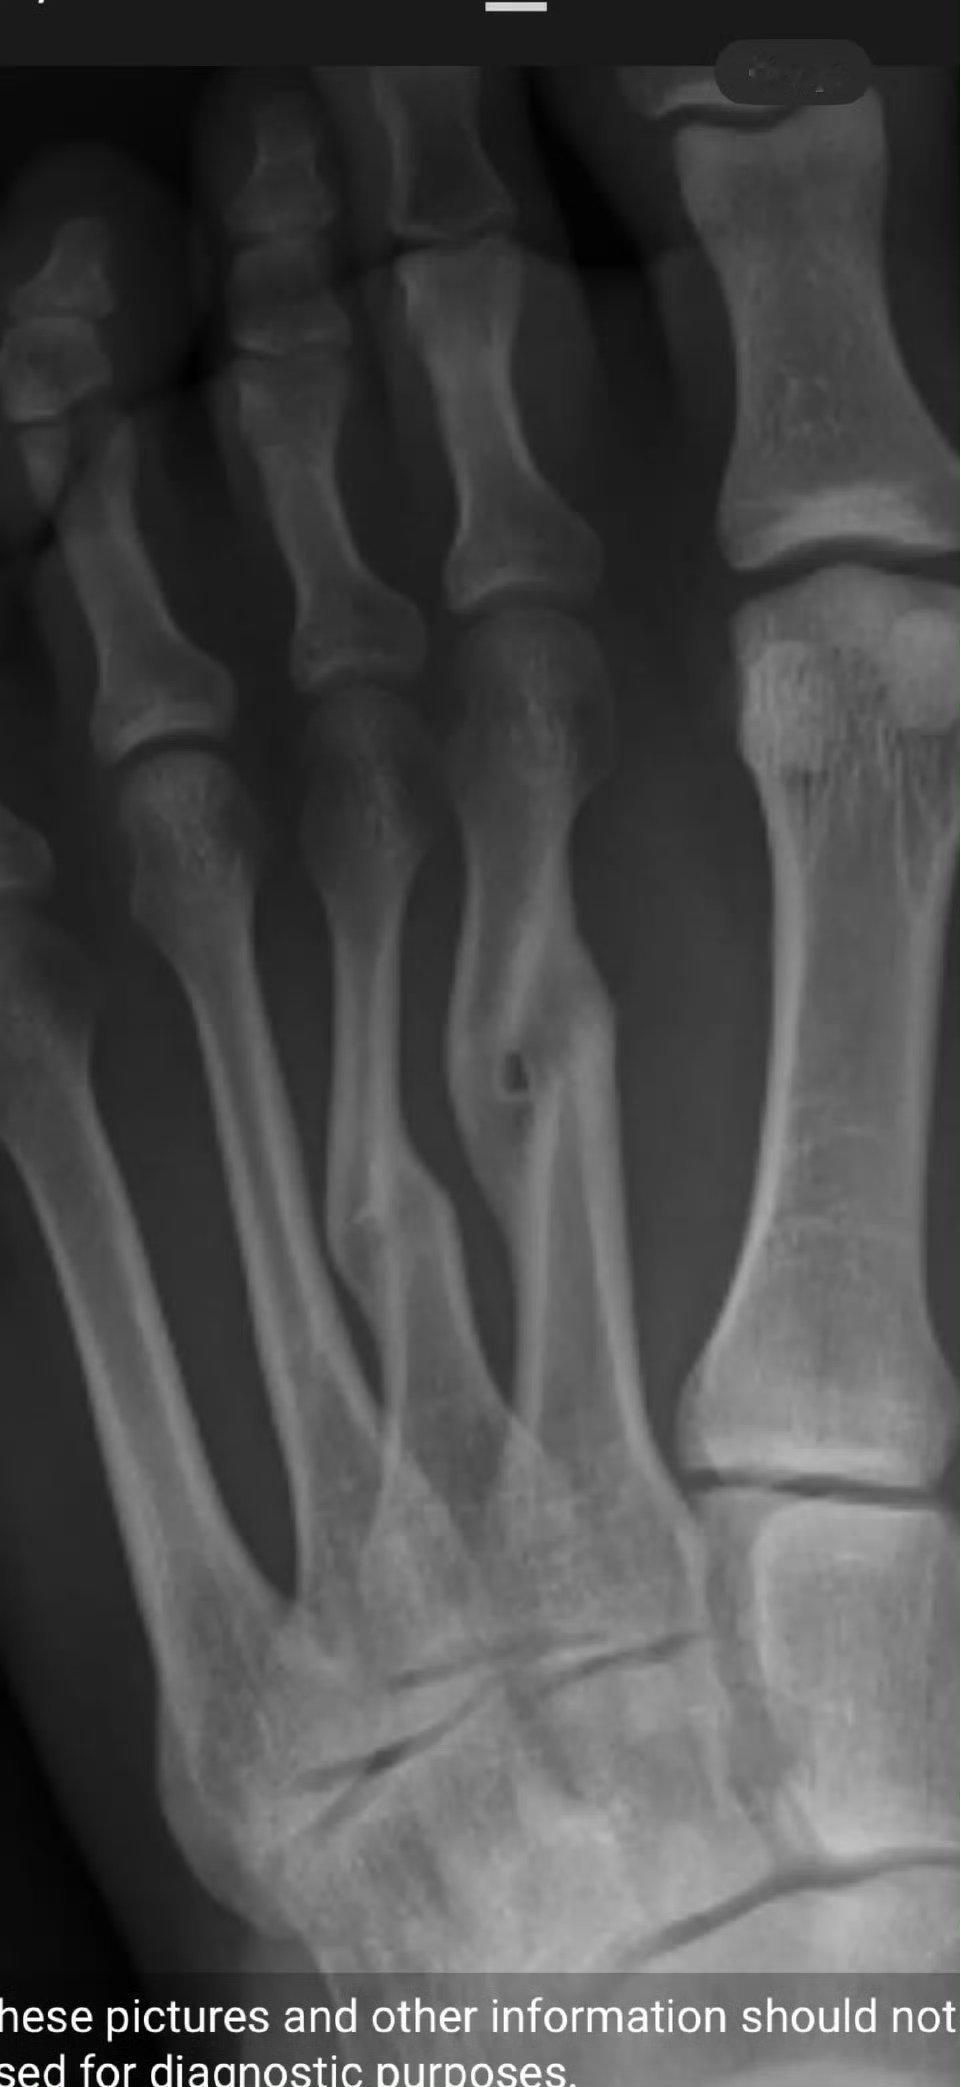

网友:脚砸伤了,没管!一年后自愈了……

你这都畸形愈合了好不好

这样的骨折,不管是不可能正常走路的。只需要复位固定不扰动(夹板,或者石膏)拐杖,护理3个月即可。

错位愈合,我有个脚趾也是

当初没拿木条固定好,还是歪了点

对位这么差也能长好属于奇迹了

畸形愈合

这个不是很严重的,我见过5根全折而且错位的,因为经济困难没有处理,就那样自己愈合了,除了外观不好看没有遗留其他毛病。其实仔细想想,脚上骨头骨折落毛病的几率不大,参考以前缠足的小脚老太太

没矫正,骨头增生了,畸形了吧

要不是我同一位置骨折我就信了,这叫跖骨,我当时是断了一根,而且还没有完全断开,根本下不了地,打石膏瘸了大半年才勉强走路,每隔三个月照片来看,骨痂长得相当慢,这TM都断来歪成啥样了,一年就能长好?别忽悠不懂的人好嘛[狗头]

骨头确实会自动连接起来,但是不去医院就行归位处理,断口会错位连接,造成畸形,